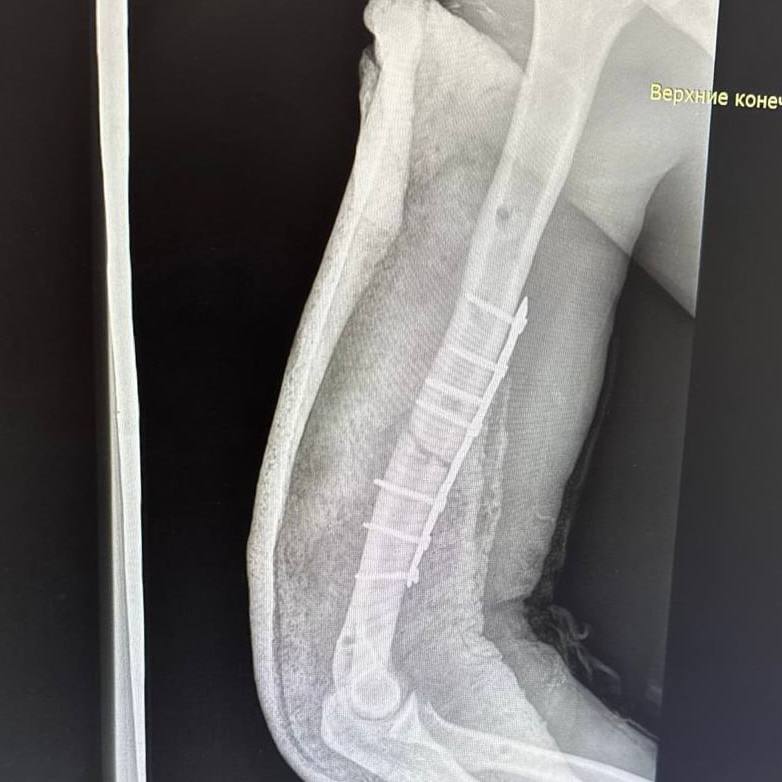

После обследования пациента экстренно прооперировали. Пациенту диагностировали множественные переломы костей лица, рёбер в нескольких местах, правой и левой плечевых костей, седалищной кости и правой голени. Правое лёгкое оказалось разорванным, в плевральной полости скопились воздух и кровь. В ходе операции пациента стабилизировали, установили аппараты внешней фиксации и перевели в реанимацию травмоцентра.

В течение месяца пациенту провели пять операций остеосинтеза. Хирурги поэтапно возвращали смещённые костные отломки в правильное анатомическое положение и фиксировали их.